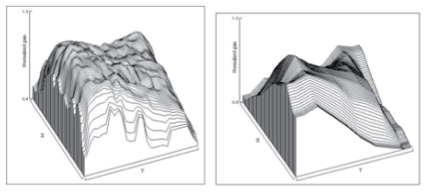

Purpose : Recent simultaneous vision simulators (SimVis) rely on the principle of temporal multiplexing of optotunable lenses (TL): Image components from different foci are superimposed to match the thru-focus optical quality of specific multifocal patterns. If sufficiently fast, the retinal images appear static. The temporal physical and perceptual aspects of temporal multiplexing are experimentally evaluated. |

In this work, we propose a novel 4D reconstruction method for PET which is based on spatiotemporal total variation (ST-TV). The ST-TV method takes advantage of image redundancies in 4D and was efficiently implemented using the split Bregman formulation, which has been shown to be optimal for decreasing noise while maintaining image quality. To evaluate the proposed approach we simulated data for a dynamic numerical phantom with different number of counts to mimic high and low Signal-to-Noise Ratio (SNR) scenarios.

| ABSTRACT | Dynamic PET images suffer from low signaltonoise ratio (SNR), especially for fast contrast uptake measurements due to the small number of counts available in those time frames. In this work, we propose a 4D reconstruction method based on spatiotemporal total variation (STTV) which takes advantage of image redundancies in 4D. The 4D STTV method was efficiently implemented using the Split Bregman formulation, which has been shown to be optimal for decreasing noise while maintaining image quality. To evaluate the proposed approach we acquired listmode data from a NEMA image quality phantom in a preclinical PET/CT scanner. |